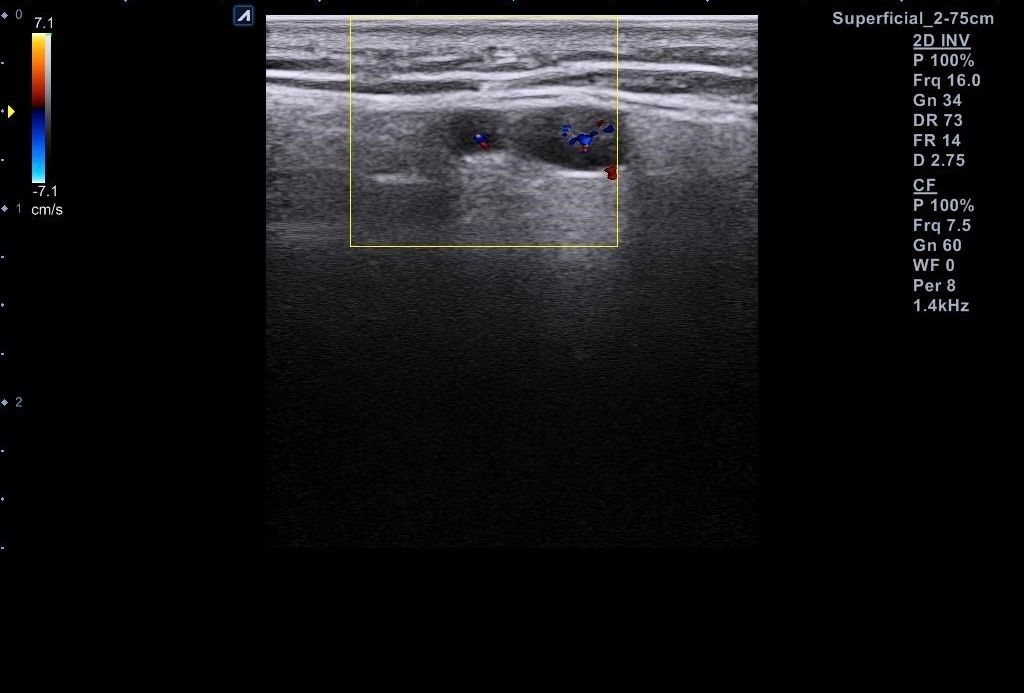

근데 병원에서 지방종이 아니라 임파선 같다고 일단 초음파 본다고 하시고 초음파를 봤는데 의사선생님이 귀 옆에 있는 임파선은 괜찮은데 아래에 있는 임파선이 초음파로 볼때 모양이랑 뭐가 조금 이상하다고 하시면서 대학병원 가보라고 소견서를 써주셨습니다 (소견서랑 초음파사진 첨부할게요)

설명들을때 기억상으로는 1 2번째 초음파사진이 귀 아래였던 거 같아요

• 1번 째 사진

소견서에 따르면, 귀주위 임파선 비대가 있는 환자로서 초음파상 1cm 미만이지만 무증상에 hypervascular하고 귀 밑은 stalk이 잘 안 보인다고 언급되어 있습니다. 크기가 크지 않고 경계가 불규칙하지는 않아 악성의 가능성은 높지 않다고 판단 됩니다. 안내받으신대로 추가검사 및 추적관찰 하시기 바랍니다.